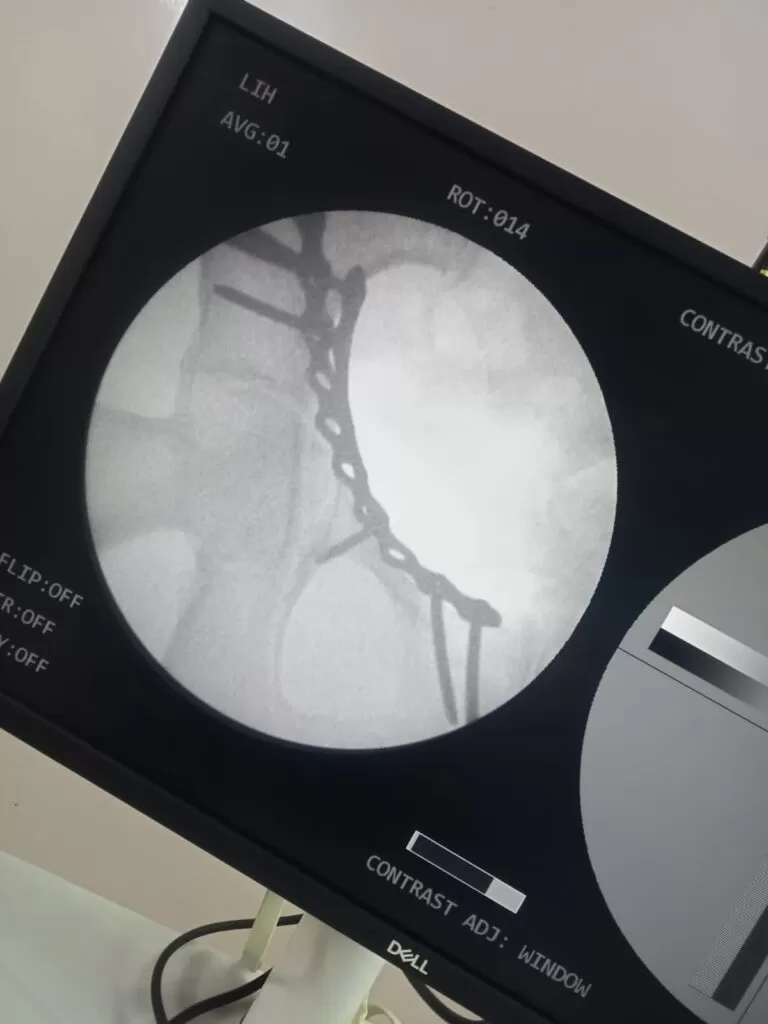

Mrs. Marzeena

Name: Mrs. Marzeena

Date of Operation: 03 Mar 2024

Age: 53 Years